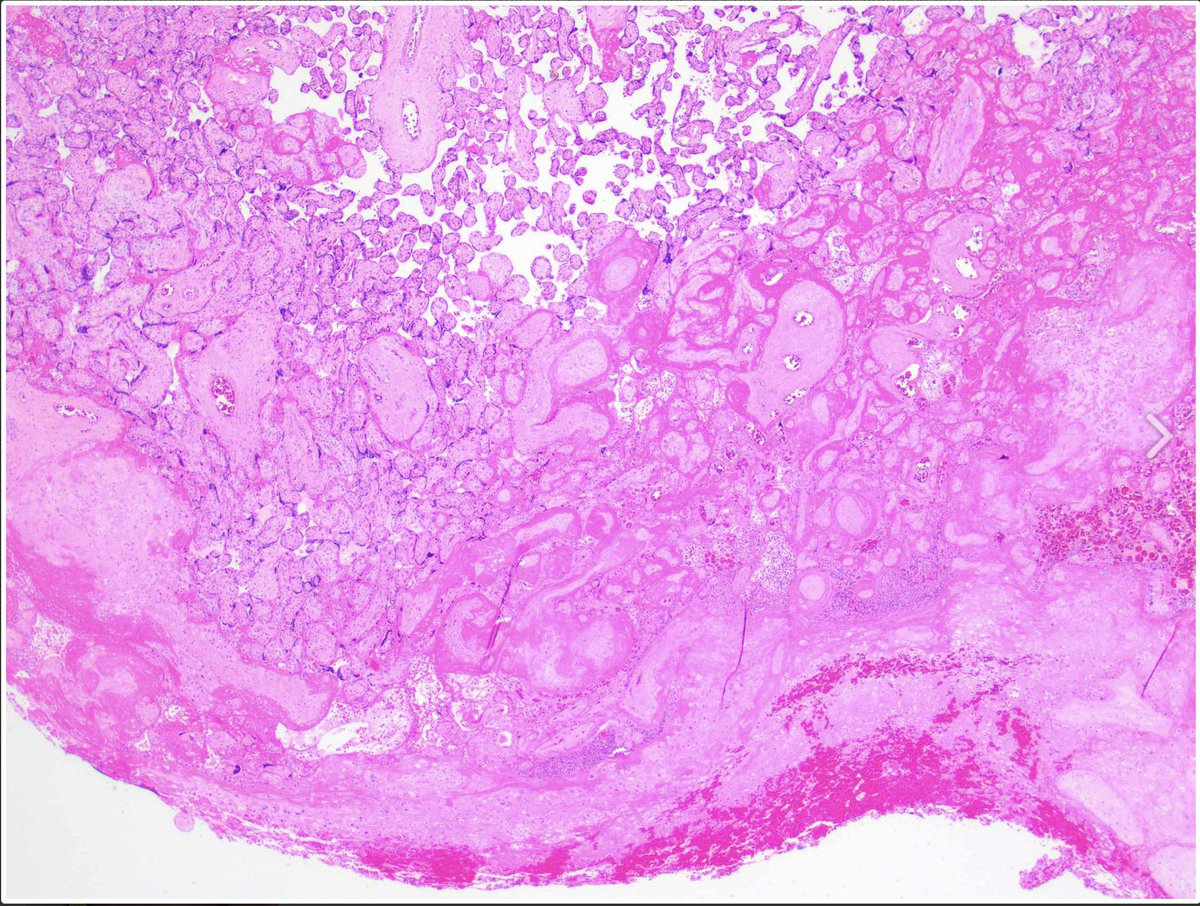

Case of the Week 🧬 65-year-old woman with a new brown macule on the cheek. Skin shave biopsy shown. What’s the diagnosis? 🔍